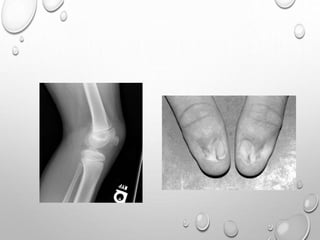

• 1. DYSPLASTIC OR SQUARE

ILIAC BONES

2. NARROW SACRO-SCIATIC

NOTCHES

3. FLAT BILATERAL

ACETABULAR ROOFS

4. SHORT BOTH FEMORAL

NECKS

5. CHAMPAGNE GLASS-

SHAPED PELVIC CAVITY

DISTAL PHALANGES ARE TAPERED , HYPOPLASTIC

NAIL – 80-90% OF PATIENTS HAVE NAIL ABNORMALITIES

BILATERALLY SYMMETRICAL

WITH ABSENT OR DYSPLASTIC NAILS.

THIS FINDING IS PRESENT AT BIRTH.

PELVIS : BILATERAL POSTERIOR ILIAC HORNS ORIGINATE FROM

SEPARATE

OSSIFICATION CENTER…..PATHOGNOMONIC

KNEE : HYPOPLASTIC OR ABSENT PATELLA